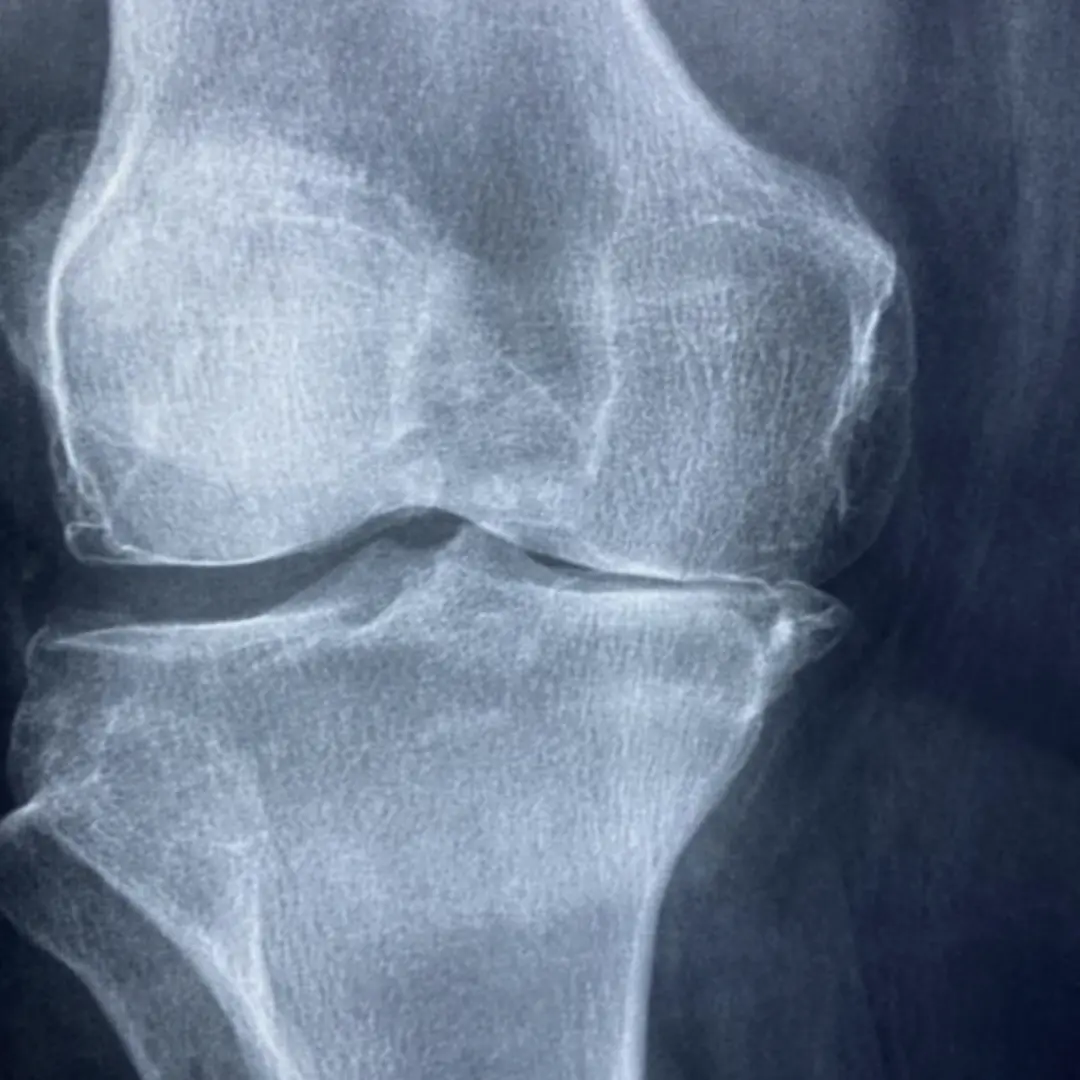

콘드로이친(Chondroitin)은 우리 몸의 연골, 인대, 힘줄, 피부 등 결합 조직에 풍부하게 존재하는 성분입니다. 특히 연골의 주요 구성 성분 중 하나인 프로테오글리칸을 구성하는 핵심 성분이죠. 연골은 관절의 충격을 흡수하고 뼈와 뼈 사이의 마찰을 줄여주는 쿠션 역할을 하는데, 이 연골의 탄력성과 수분 유지를 돕는 것이 바로 콘드로이친입니다.

콘드로이친은 우리 몸에서 자연적으로 생성되지만, 나이가 들면서 그 생성량이 점차 줄어들게 됩니다. 이렇게 콘드로이친이 부족해지면 연골이 약해지고 수분을 잃어 탄력성을 잃게 되며, 결국 연골이 손상되어 관절 통증과 염증을 유발하는 퇴행성 관절염으로 이어질 수 있어요.